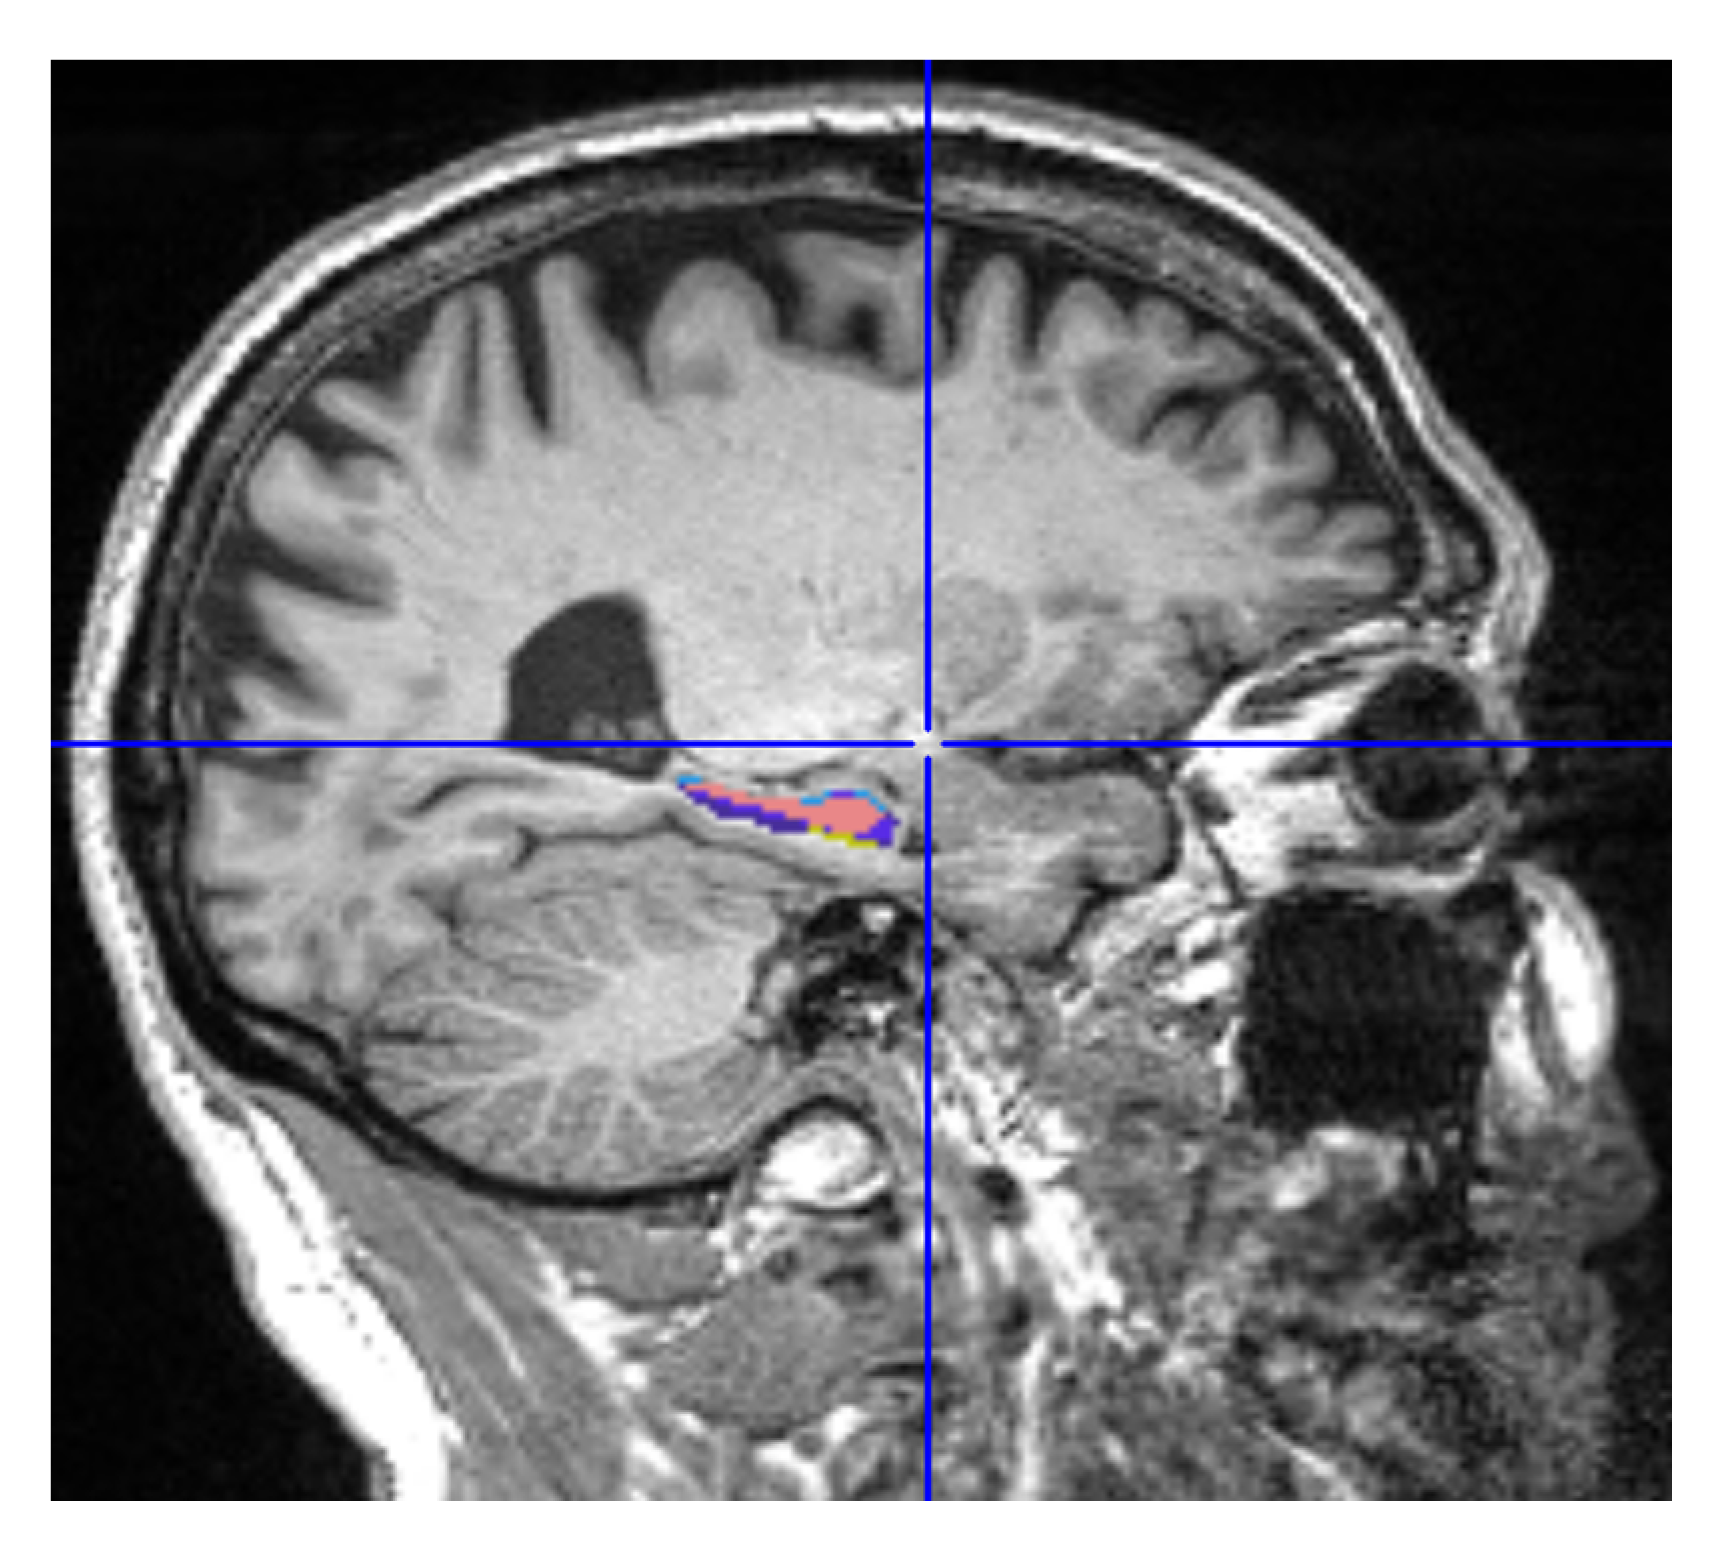

2.4. Hippocampus Segmentation

MRIcron is a cross-platform image viewer for the Nifti format. It can import several layers of images, produce volume renderings, and draw volumes of interest. It also incorporates Node Package Manager (NPM) for statistics and dcm2nii for converting DICOM images to Nifti format. We employed MRIcron to segment the data [17,18]. The complete brain scan is the data set obtained from ADNI. MRI data were processed by this program to obtain the ROI, which yielded only the hippocampus region with its original grey intensities preserved. We overlaid the Winterburn segmentation mask generated by volBrain on the original MRI and maintained the area beneath the mask, removing the pixels beyond the mask boundary as shown in Figure 4.

Figure 4.

Segmented Hippocampus volume viewed in MATLAB.